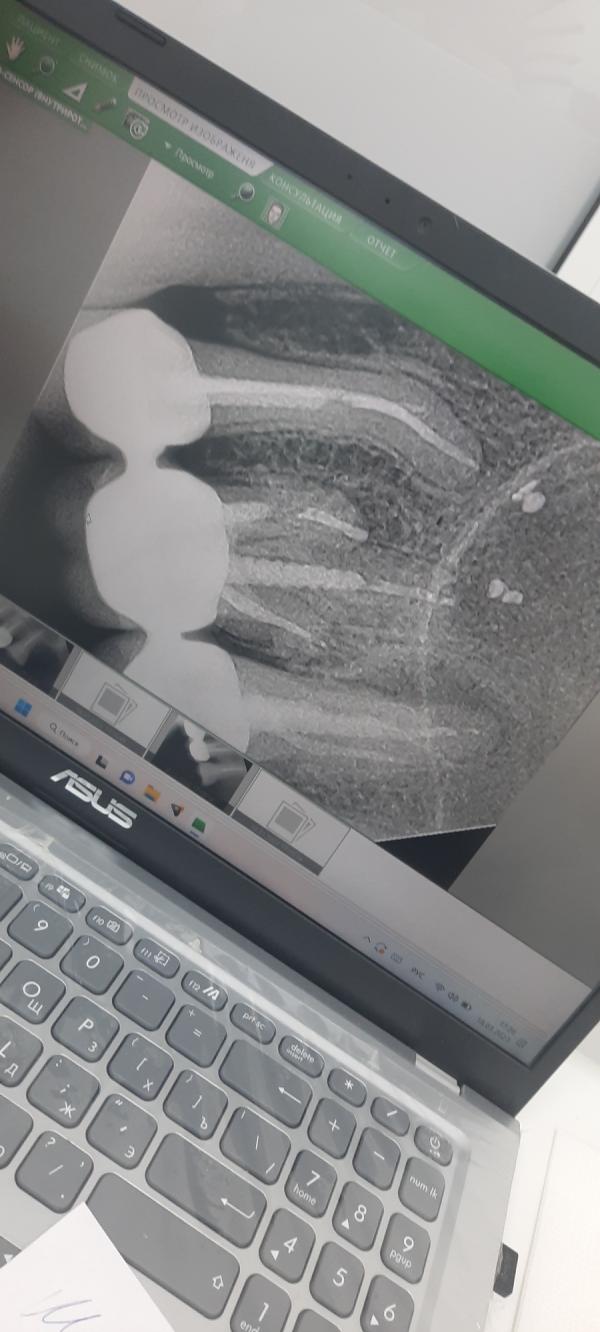

Девочки у меня острые боли зуба, записалась Бего сегодня на удаление, думала зуб мудрости болит, оказалось под коронкой болят, год может прошел только ,воспаление говорят, а так девушка которая делала она щас в селе, я будто умираю, как протерпеть до вторника,ещё запись полная у нее, тока ночью сможет принять, я два дня на немесиле, я не могу это терпеть, 😭🥺🥺🥺не проходит боль

У меня не болит но опухла щека, врач сказал что кусочек корня остался и воспаление поэтому , тоже зуб под коронкой. Сказал делать полоскание сода соль и йод , не греть и если не пройдёт то будет удалять. Но у меня проходит , рахат-лукум спадает

, мучалась с болью под коронкой. Оказывается еда туда попадала , и зуб внутри сгнил , пришлось распилить коронку и зуб удалить.